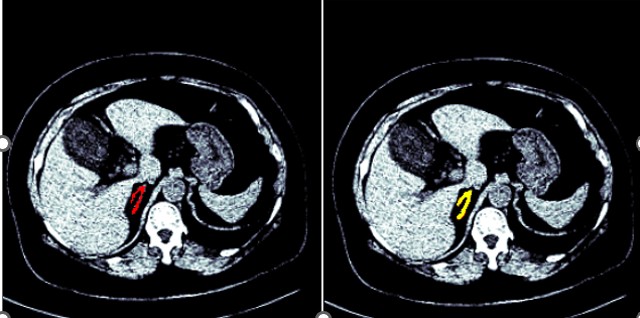

Figures 1 and 2 show the segmented model output for both right and left adrenal gland from a CT scan image from the AMOS dataset.

Figure 1: Segmentation of a right adrenal gland (AMOS dataset)